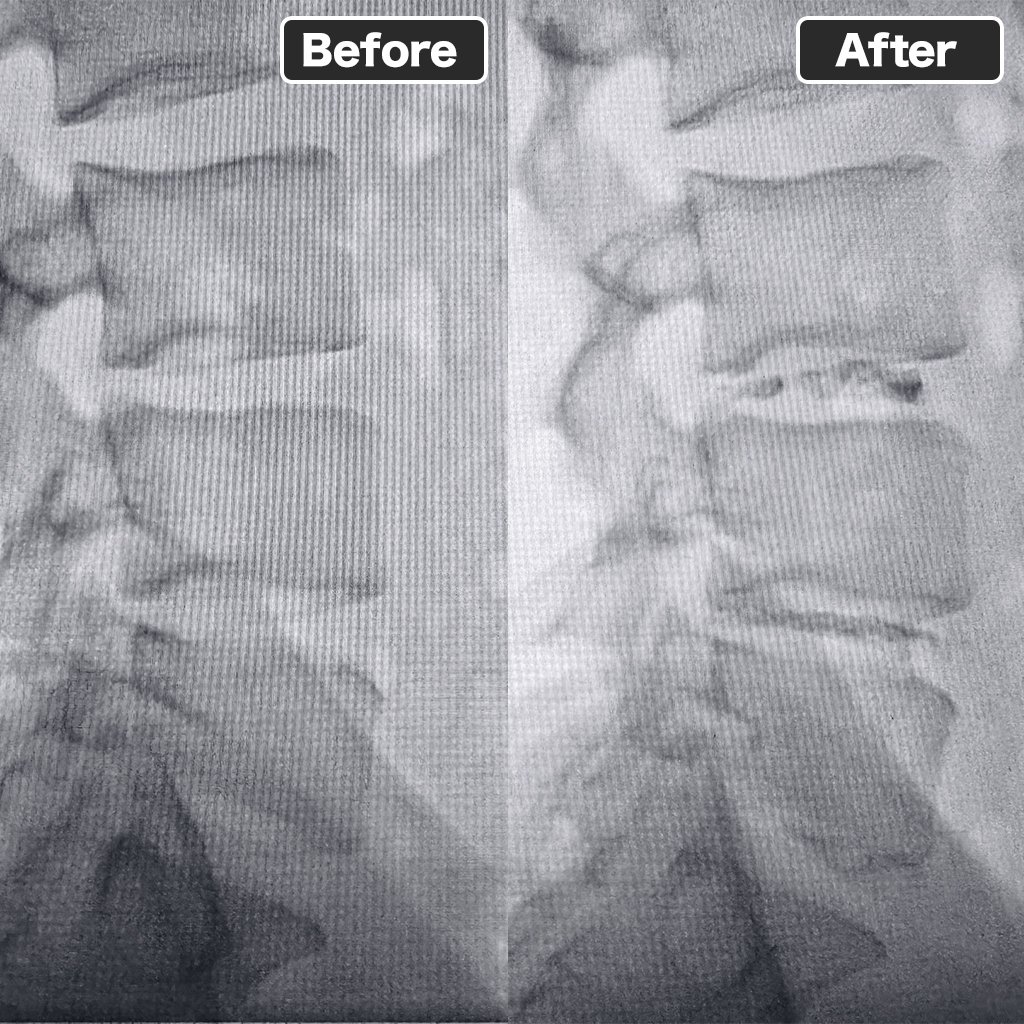

治療前後のレントゲン

治療前後のレントゲン写真になります。左側が治療前、右側が治療後です。